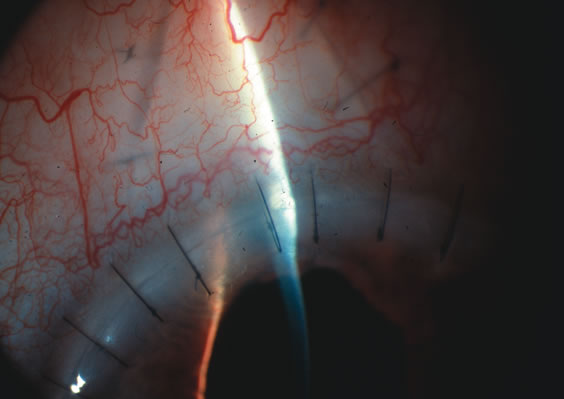

In years past, patients with both cataract and glaucoma frequently provided overwhelming surgical challenges for the ophthalmologist. The ability to carry out phacoemulsification through a 3.2-mm corneal incision along with inserting a foldable IOL is a vast improvement over 11-mm incisions that were common a decade ago (Fig. 1). The anatomical and inflammatory changes to the eye are less with small incision techniques, improving the likelihood of success with concomitant glaucoma surgery. Pharmacologic inhibition of fibrosis along with postoperative wound revision increases the long-term success rate of filtration surgery when combined with lens extraction. (Fig. 2). The learning curve may be steep at times, but the blending of cataract and glaucoma surgical skills slowly falls into place as the surgeon constantly learns and upgrades his or her technique.

Fig. 1. The anatomic advantage of small incision cataract surgery for the glaucoma patient. A. Long-term bleb function with a large cataract incision is difficult to achieve with either ECCE-trabeculectomy or trabeculectomy followed later by ECCE. This bleb failed to form sufficiently when combined with large incision ECCE. The inflammation, bleeding, and long-term wound healing with stimulation of fibroblasts associated with this technique are more likely to cause bleb failure. In addition, the increased iris manipulation necessary to deliver the nucleus and subsequent iris repair adds to the long-term breakdown of the blood aqueous barrier. B and C. Two-site phacotrabeculectomy has the advantage of small incision cataract surgery combined with separate site trabeculectomy. The incision size is one third the size of the standard ECCE. The inflammation is less severe, and cataract wound healing is confined to the temporal area. Visual rehabilitation with phacoemulsification and foldable IOL is much faster. Phacoemulsification allows successful lens extraction even in the unfriendly environment of a smaller pupil compared with ECCE. The trabeculectomy is performed in an entirely different site, well away from the wound healing associated with temporal phacoemulsification. The likelihood of this filter functioning long-term is greater than with ECCE-trabeculectomy. D. The surgeon also has the option of single-site phacotrabeculectomy with foldable IOL. Both the lens extraction and trabeculectomy are performed through one small 3.5-mm limbal incision.